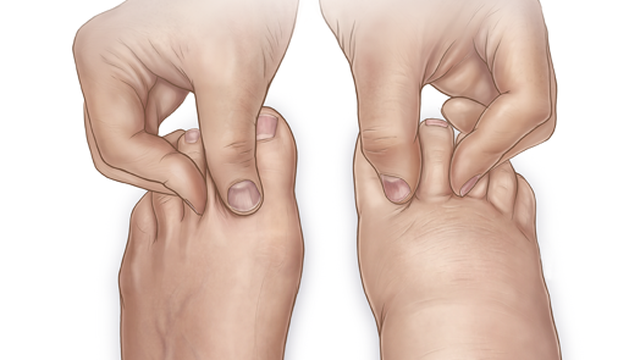

Physical exam findings to differentiate the diagnosis of chronic venous insufficiency from lymphedema (name two)

Suggestive of chronic venous insufficiency -

1. Pain relief with leg elevation

2. Symmetric swelling of legs bilaterally

3. Increase of swelling at night

4. Negative Kaposi-Stemmer sign (skin of basal dorsum of second toe cannot be pinched as a fold between the fingers)